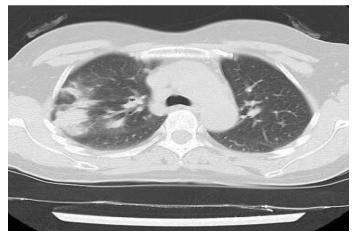

▎间质性肺炎

很多间质性肺炎都会表现为胸膜下为主的病灶,特别是隐源性机化性肺炎,需要结合临床表现具体分析。

下图是嗜酸细胞性肺炎。